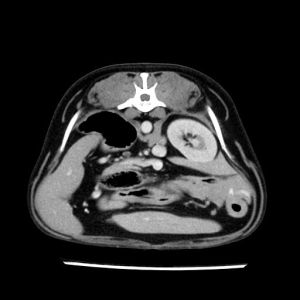

La lesione focale epatica , la ceus,la Tac e il chirurgo .